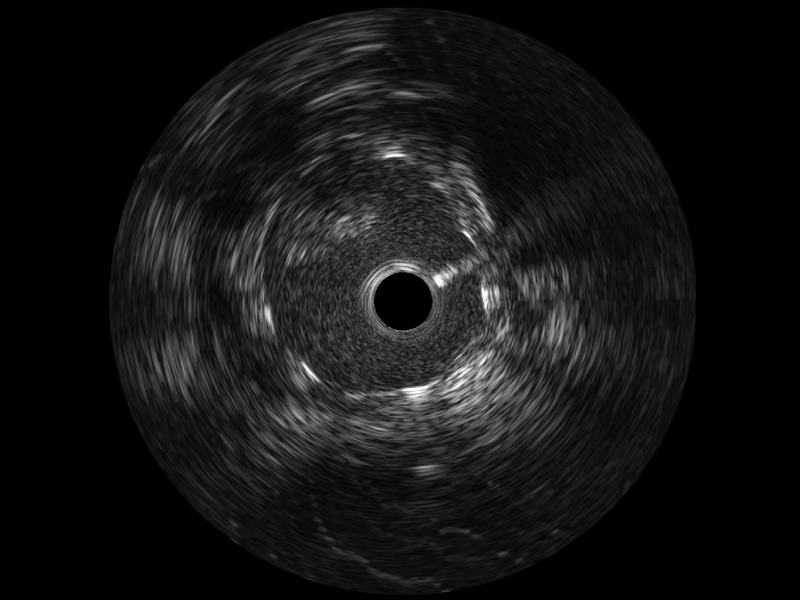

• 米兰官方网站宽频IVUS图像

• 传统IVUS图像

对比传统IVUS导管成像,米兰官方网站宽频IVUS图像的近场支架梁显影更细腻,远场中膜外血管仍清晰可辨,兼顾远中近,兼顾分辨力与穿透深度